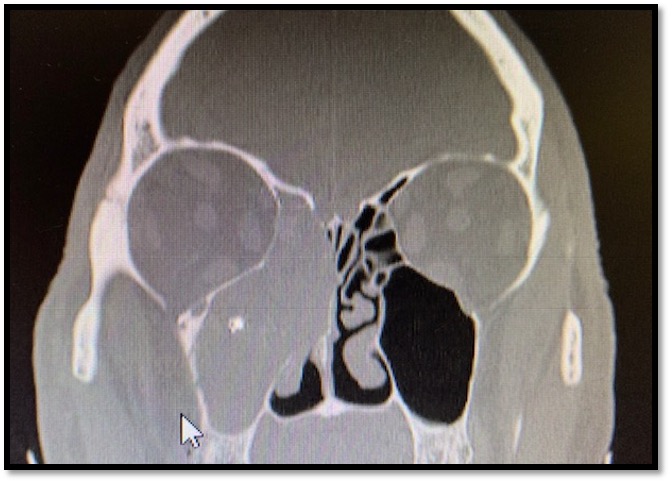

La TAC dei seni paranasali evidenzia un opacamento iperdenso del seno mascellare di destra con marginale coinvolgimento etmoidale.

All’interno del seno sono evidenti microcalcificazioni. La parete mediale del seno appare assottigliata, bombata all’interno della fossa nasale e ampiamente erosa.